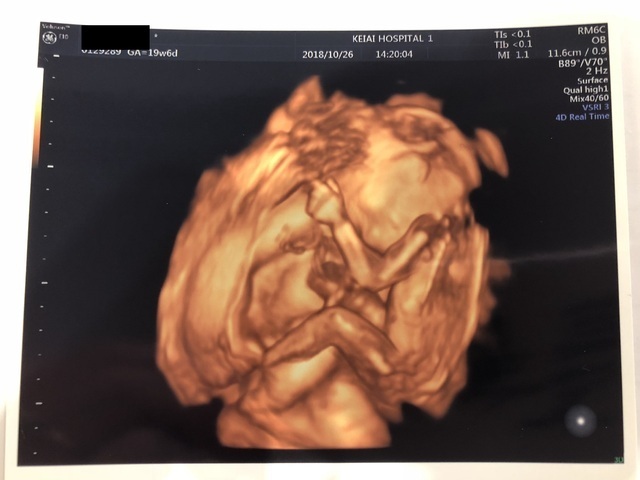

20週0日(20w0d・男の子)|saori 0104 さん

エコー写真撮影時のエピソード:

安定期に入った時に新居に引越しをし、病院を変えました。その時、初めての妊婦健診が胎児スクリーニングの時でした。胎児スクリーニングでは3Dエコーが見られるということで、初めての3Dエコーに私も主人も大興奮でした。助産師さんからは「この時期はみんな買おが一緒ですよ」と言われましたが、「このほっぺたが主人に似てる!」「鼻は私に似てるよね!」などと助産師さんお構いなしに盛り上がってしまったのはいい想い出です。

先程も記載した通り安定期に入った20週の頃にエコーを撮りましたが、私は妊娠悪阻で会社を1ヶ月半休職し、この頃は復帰して1ヶ月程たったときでした。今思うと1番体が動きやすく仕事もバリバリとやっていましたが、貧血が酷く電車の中で倒れることもしばしばありました。主人にはその度心配をかけさせてしまい、私の体調をすごく気にかけてくれました。健診には毎回ついてきてくれるので、一緒に赤ちゃんが産まれてきてくれることを楽しみにしてくれているんだなと感じます。